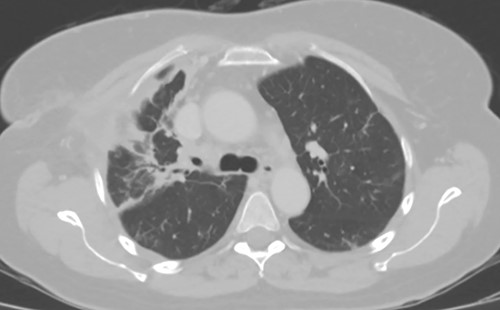

Three weeks following her initial COVID-19 diagnosis, she presented to the hospital with ongoing symptoms and was found to have a right hydropneumothorax and cavitary lesion with parenchymal destruction (Fig. 1). She was treated with broad-spectrum antibiotics and percutaneous chest tube drainage, which showed a continuous one- to two-column air leak. Her pleural fluid grew methicillin-sensitive S. aureus (MSSA). Bronchoscopy revealed mucosal edema and erythema, particularly in the right upper lobe. Despite treatment, she had a persistent air leak, and she was transferred to our facility for further management.

(A) Plain film of chest showing apical hydropneumothorax. (B) Computed tomography axial image demonstrating a complex hydropneumothorax with significant right sided parenchymal infiltrate.